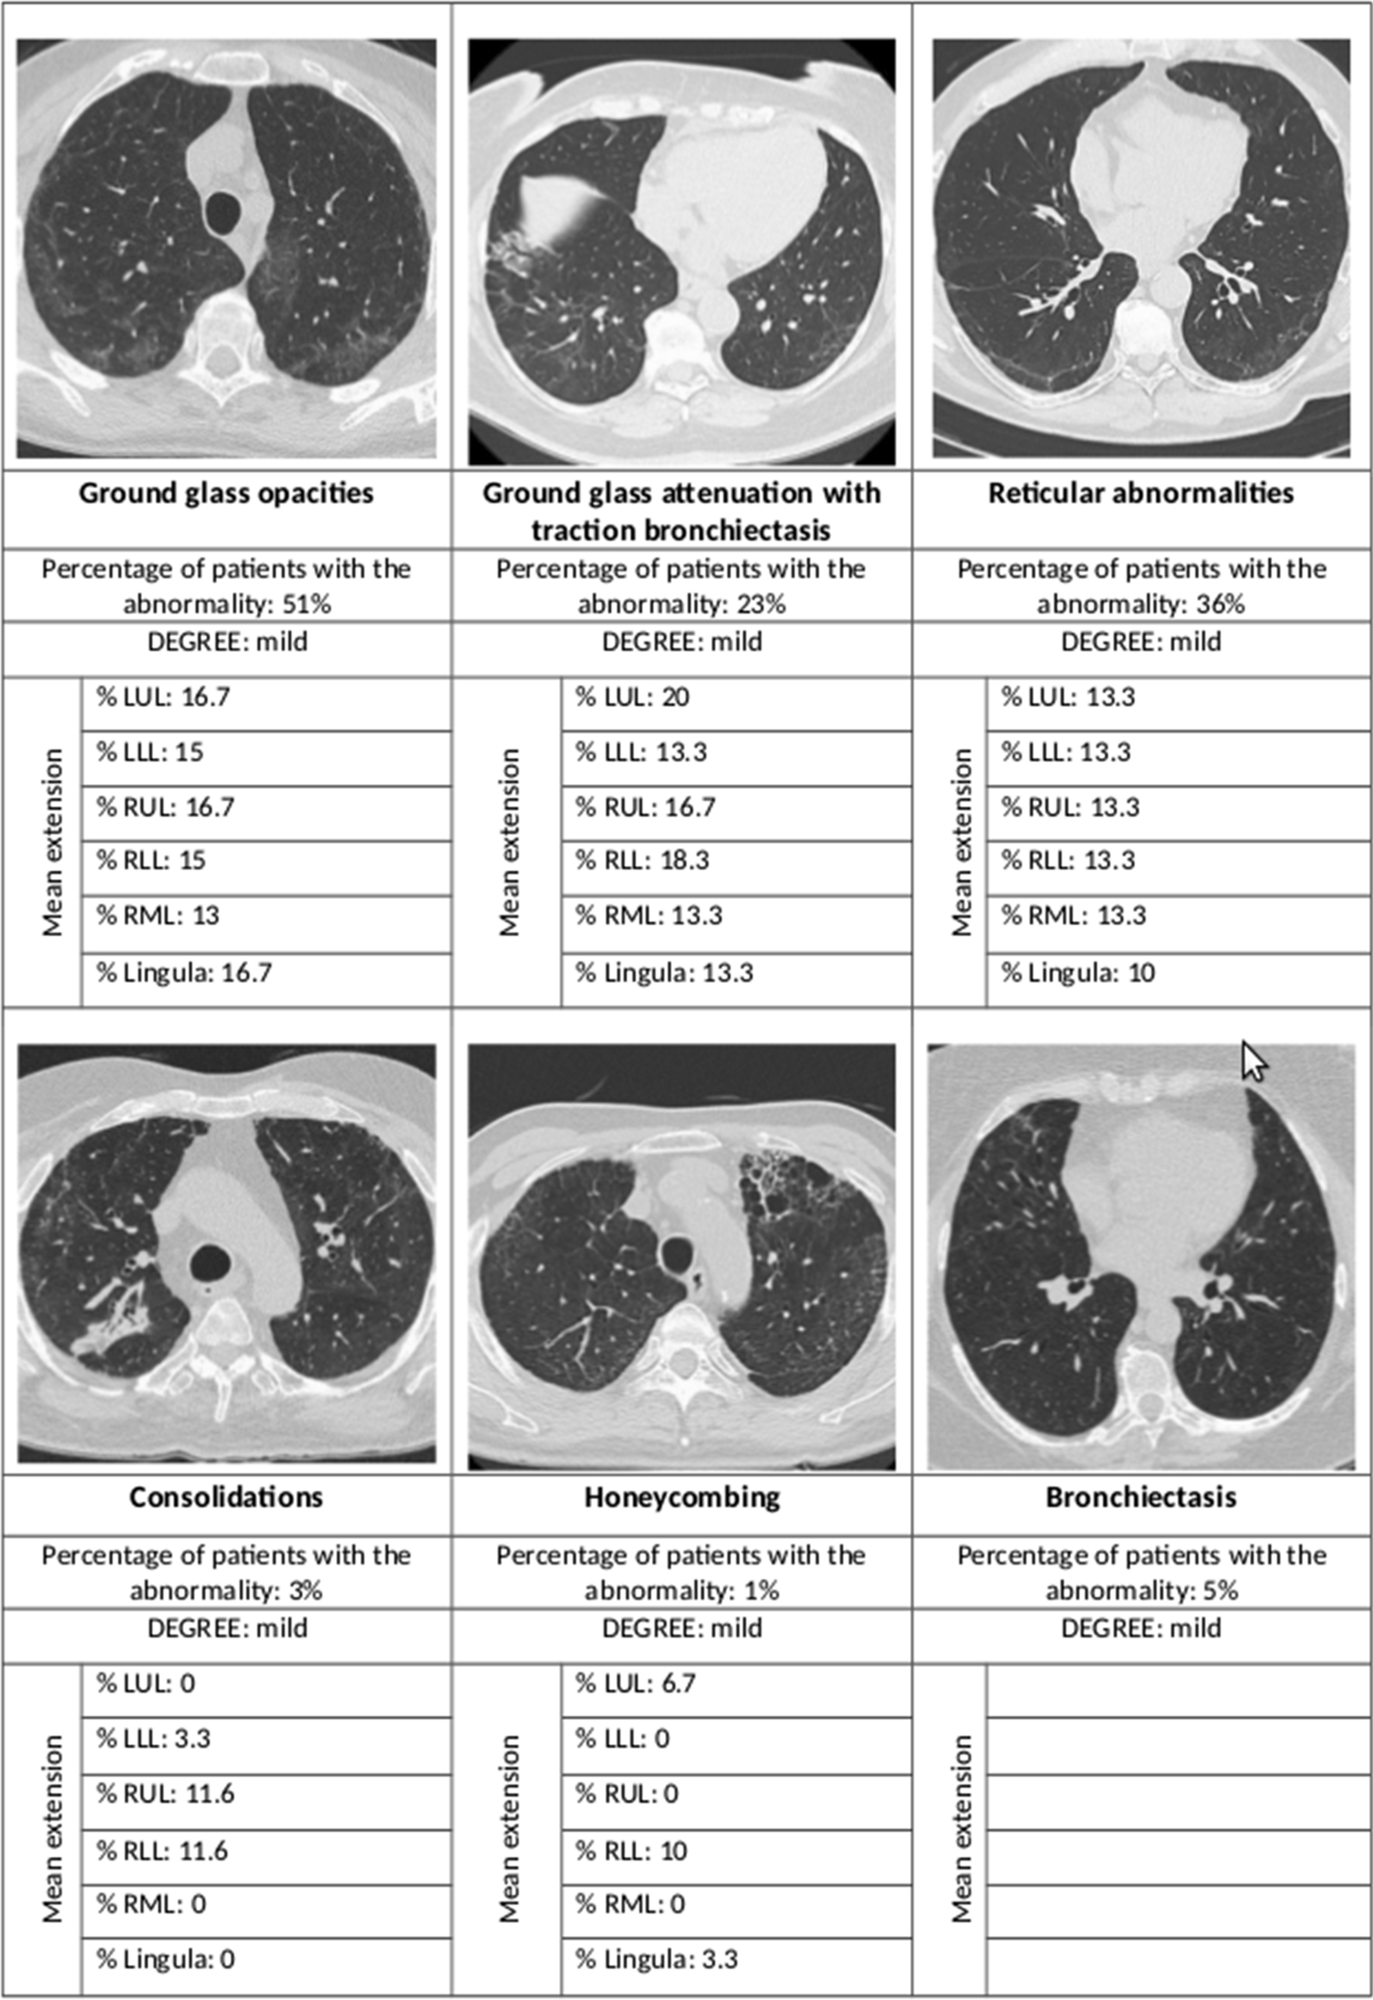

Summary of the main radiological abnormalities and their extension according to the lung lobe involved. LUL left upper lobe, LLL left lower lobe, RUL right upper lobe, RLL right lower lobe, RML right middle lobe

Most of the high-resolution CT (HRCT) scans showed interstitial lung changes; over half showed ground-glass opacities, over a third had reticular abnormalities, while less than 5% each showed consolidations and honeycombing. In 44% the ground glass opacities were accompanied by traction bronchiectasis or bronchiectasis.

The findings show that fibrosis of the lung is an uncommon finding after SARS-CoV-2 pneumonia requiring hospitalization, with only 1% of patients showing this complication at 12 months from discharge. Most cases showed other mild interstitial results, mostly ground-glass opacities and reticular abnormalities, mainly within a single lobe and limited in extent.